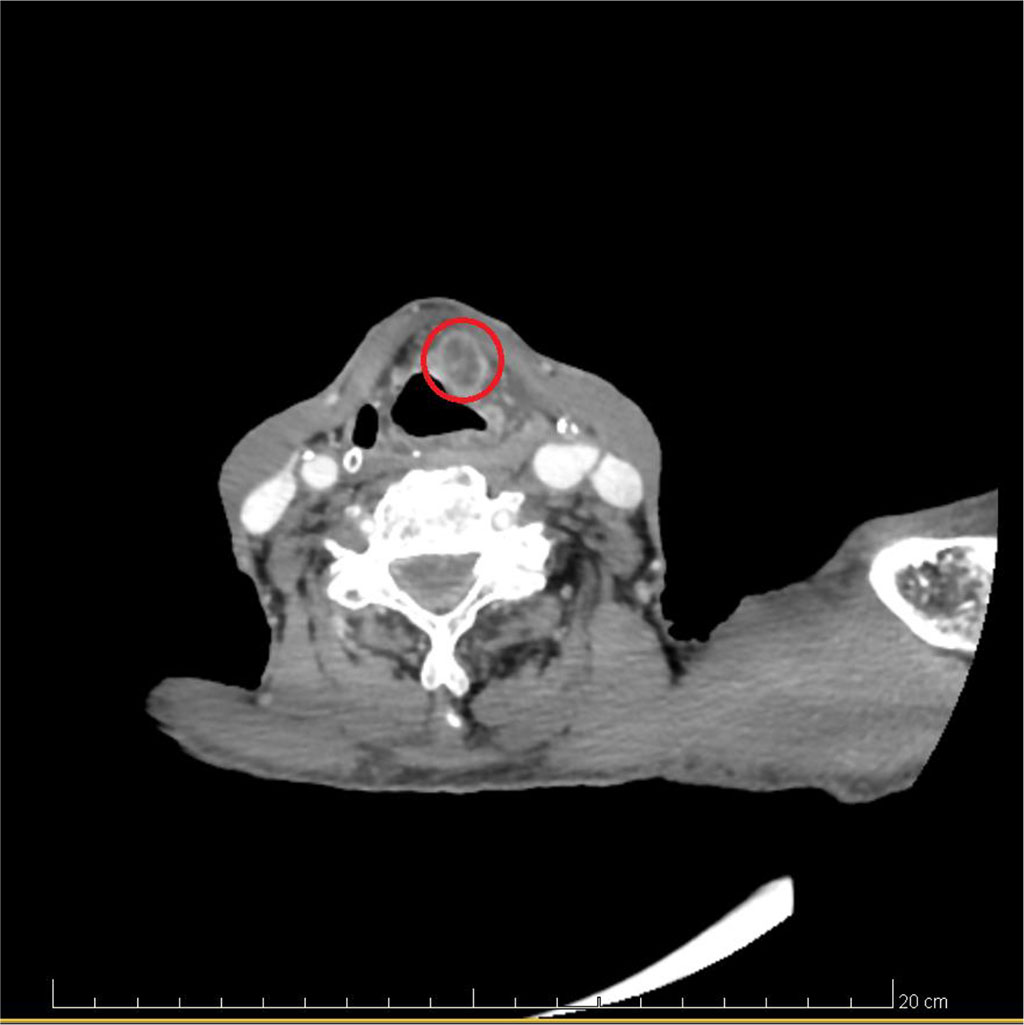

To further evaluate the patient, a CT scan of the larynx was ordered with intravenous contrast agent [Figure 1.]. The CT scan revealed a pathological mass with disintegrative features measuring approximately 24 x 10 x 37 mm within the vestibular fold on the left side. The lower pole of the mass reached the subglottic region, and the upper pole of the mass abutted the fat body without any features of thyroid cartilage destruction. There were no signs of infiltration of the spoids.

In addition, a visibly enlarged lymph node of group IIB with destructive features was found on the left side, measuring approximately 12 x 16 mm in cross-section. Single lymph nodes of groups VA and VB were also present, measuring up to 5 mm in cross-section.

Numerous massive polyps were observed on the left side of the glottis.

[Figure 1.]